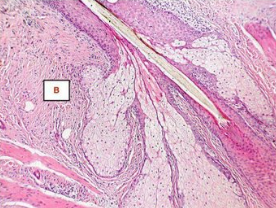

The histopathological image represents the _____ gland, which is a type of holocrine gland.